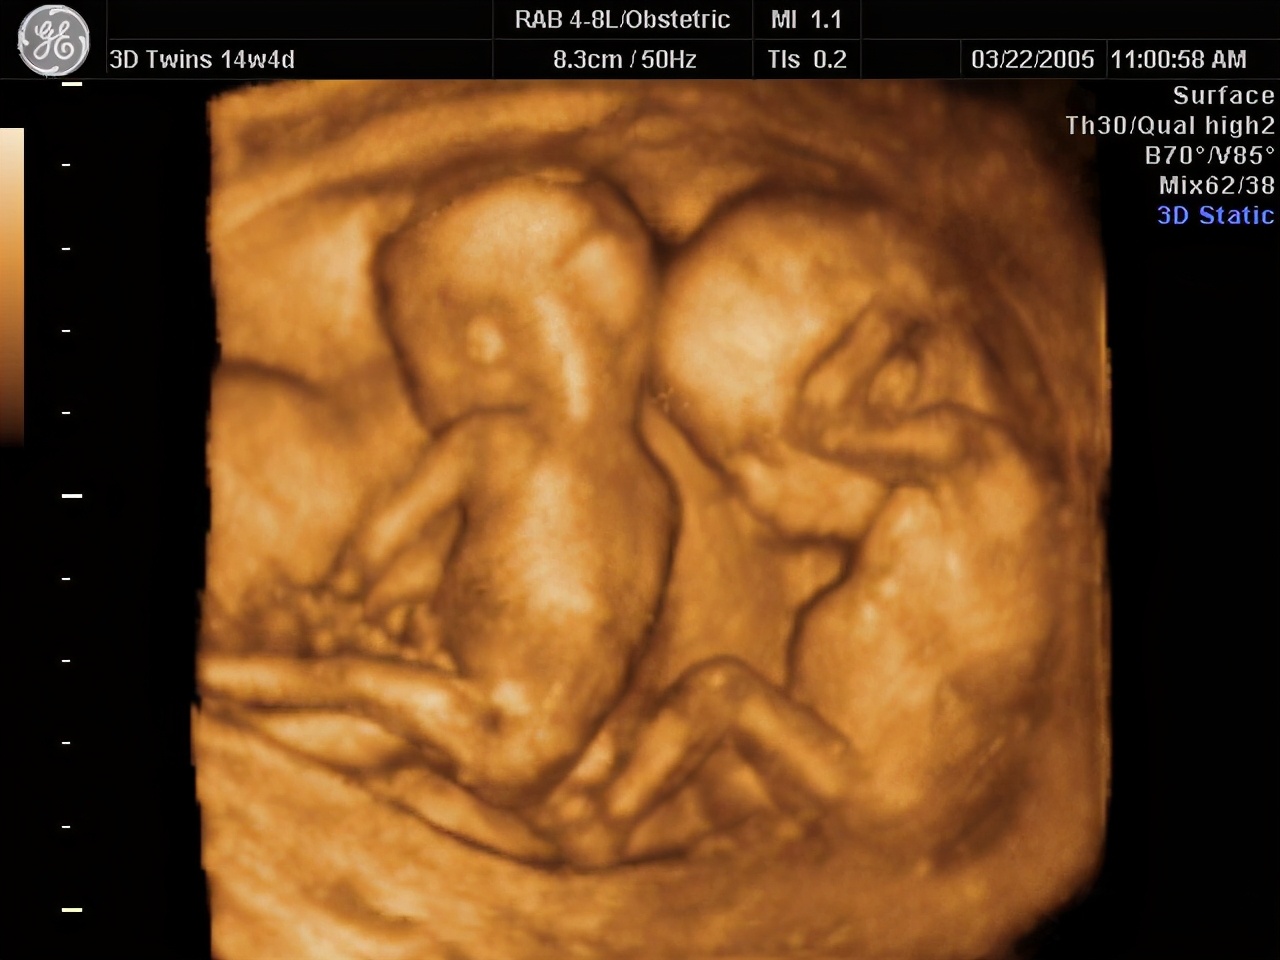

几次产检,彩虹得到的结果都是“孩子很健康”。但她依然不放心,坚持做了对自己来说“天价”的四维彩超,也没有发现孩子发育不正常。对她来说,那段时间,每次产检都像是闯了一道关。

四维彩超(资料图)。彩虹误以为其能帮助自己确认孩子健康,但四维彩超只能直观反映胎儿是否畸形。